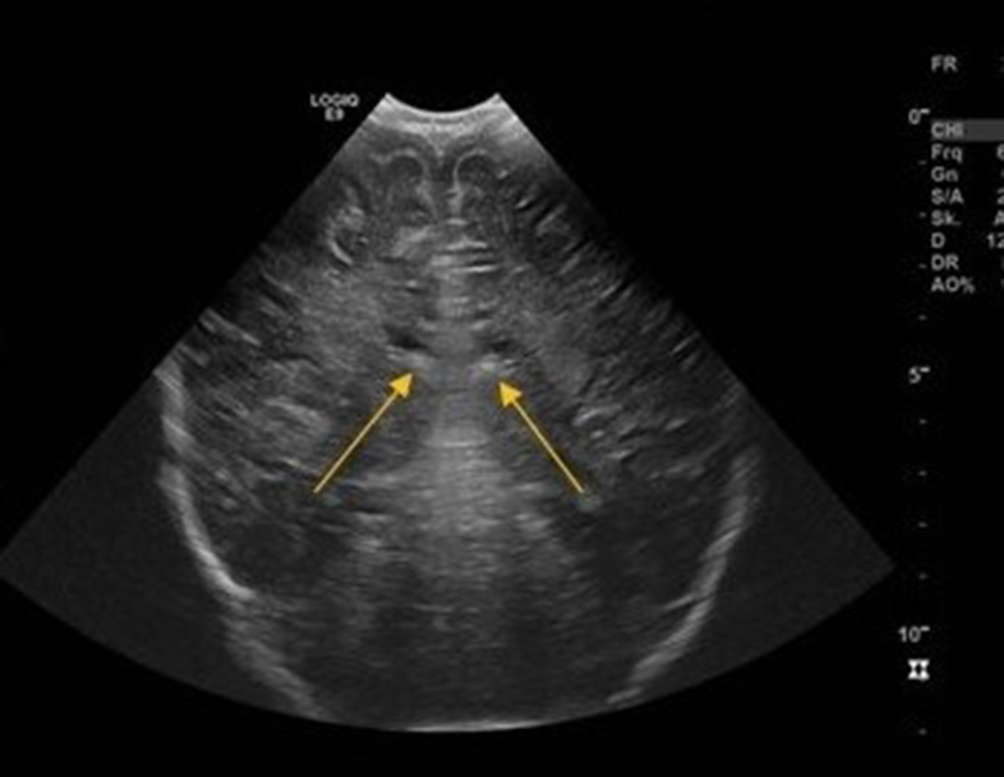

Abb. 1 (ursprüngliche Fassung)

Kraniale Sonographie, koronarer Schnitt, bei dem Patienten im Alter von sechs Monaten: angedeutete bilaterale periventrikuläre Echogenitätssteigerung (Pfeile)

Bild vergrößern